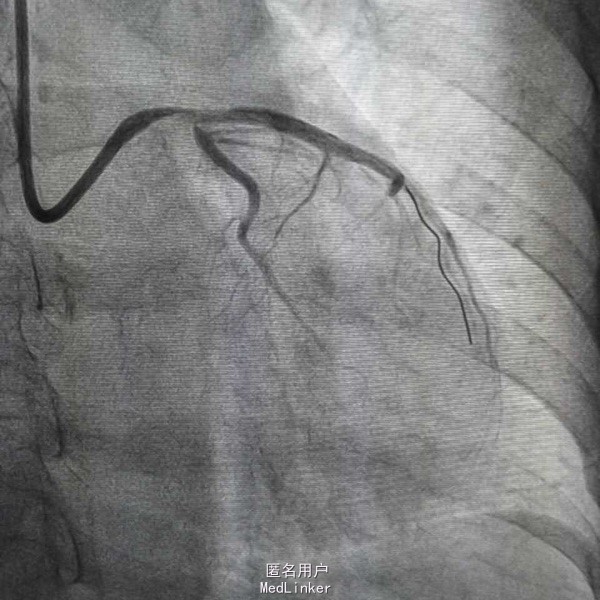

患者,女性,63岁,主因阵发性胸痛5天,加重15小时入院,既往否认高血压糖尿病史,无食物及药物过敏史,无不良嗜好。入院前一天剧烈胸痛晕厥一次,具体情况不详。

血压97/57mmHg,神清语明,口唇无发绀,颈静脉无怒张,双肺无啰音,心率82次每分,律齐,未闻及杂音,腹平软,肝脾未及,双下肢不肿。 辅查心电Il Ill avf ST段下移,avl V6 ST段抬高 白细胞14X109/L,D二聚体665ug/L,肌钙4.1ng/mL,

急性心肌梗死 心功能I级 处理,抗凝抗聚后行PCI治疗

造影示左主干闭塞,如图,预扩后快速送入支架行冠脉再通,此病人心电图很难判断左主干病变,值得警惕